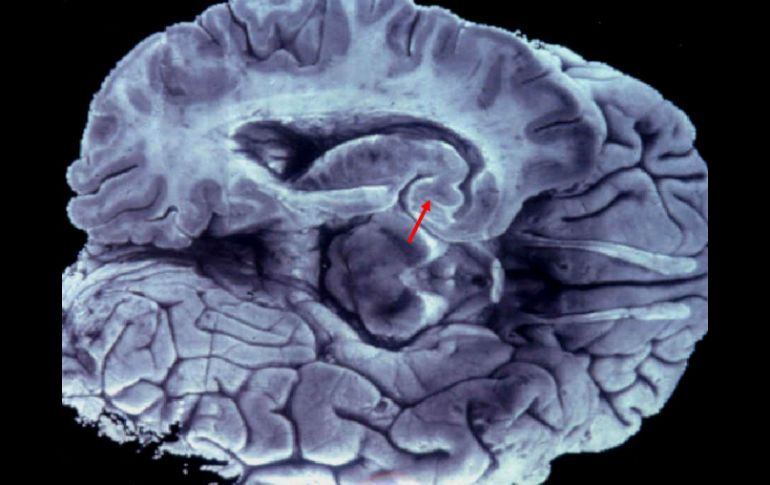

Tecnología | Esta investigación implica un gran desafío para los científicos La pérdida de memoria puede comenzar a los 45 años Detectar la edad a la que comienzan a deteriorarse la memoria es importante porque los medicamentos funcionarán en la medida en que se administren a las personas que comienzan a experimentarlo Por: REUTERS 6 de enero de 2012 - 18:23 hs Científicos buscan nuevas formas de detener el avance de la demencia en la población. EFE / LONDRES, INGLATERRA (06/ENE/2012).- La pérdida de memoria y otras funciones cerebrales puede comenzar a los 45 años, lo que implica un gran desafío para los científicos que buscan nuevas formas de detener el avance de la demencia en la población, informaron investigadores. El hallazgo de un estudio de 10 años de duración sobre más de siete mil trabajadores estatales de Gran Bretaña contradice las teorías previas de que el deterioro cognitivo no se inicia antes de los 60 años y podría tener implicancias de largo alcance en la investigación de la demencia. Detectar la edad a la que comienzan a deteriorarse la memoria, el razonamiento y las habilidades de comprensión es importante porque los medicamentos funcionarán en la medida en que se administren a las personas en cuanto comienzan a experimentar el deterioro mental. Un puñado de nuevas medicinas para la enfermedad de Alzheimer, la forma más común de demencia, están siendo sometidos a ensayos clínicos, pero las expectativas son bajas y algunos expertos temen que los nuevos fármacos estén siendo probados en pacientes demasiado mayores para mostrar beneficios. Entre las compañías que están desarrollando medicamentos de este tipo se encuentran Eli Lilly, que está trabajando en un fármaco llamado solanezumab, y Elan y Johnson & Johnson, que está desarrollando bapineuzumab. El equipo de investigadores dirigido por Archana Singh-Manoux, del Centro para la Investigación en Epidemiología y Salud Poblacional de Francia y del University College de Londres, halló un deterioro modesto en el razonamiento mental en hombres y mujeres de 45 a 49 años. "A partir de investigaciones previas esperábamos no ver deterioro", dijo Singh-Manoux en una entrevista telefónica. Entre los sujetos de más edad del estudio, el deterioro promedio en la función cognitiva fue mayor, pero hubo una amplia variación en todas las edades. Un tercio de los individuos de 45 a 70 años no mostró deterioro durante el período estudiado. "No sucede de repente cuando uno envejece. Esa variabilidad existe mucho antes", dijo Singh-Manoux. "El próximo paso es (...) buscar relaciones con factores de riesgo", agregó. Temas Investigación científica Ciencia médica Alzheimer Lee También Conmociones cerebrales, la cuarta lesión más frecuente en partidos de la Conmebol Estudio chino revela una mutación que eleva riesgo de alzhéimer ¿Cómo se forman los recuerdos en la mente? Esto dijo Israel sobre la extradición de Zerón a México Recibe las últimas noticias en tu e-mail Todo lo que necesitas saber para comenzar tu día Registrarse implica aceptar los Términos y Condiciones